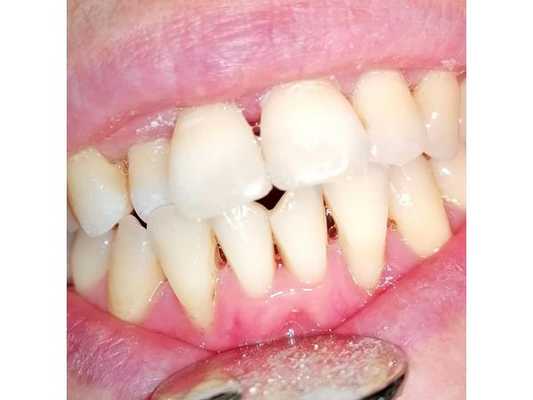

42-летний пациент обратился за стоматологической помощью по поводу неудовлетворительного вида его верхних центральных зубов и нарушения общего вида улыбки (фото 5 - 6).

Фото 5. Клинический случай №2: прицельные снимки верхних зубов перед лечением.

Фото 6. Натянутая улыбка для определения степени обнажения десен.

Учитывая тяжелую степень пародонтита, некоторые из его зубов подлежали экстракции, остальные - пародонтологическому лечению, а области дефектов зубного ряда - восстановлению посредством имплантации. Специфика пациента состояла в том, что он много путешествует, следовательно, состояние постоперационной адентии для него является неприемлемым. Кроме того, учитывая аспекты его профессии и высокую социальную активность, съемные протезы также не являлись допустимой альтернативой в данном клиническом случае. После дискуссии относительно всех возможных вариантов реабилитации, пациент остановился на концепции «Все-на-четырёх» с последующей немедленной нагрузкой титановых элементов после удаления проблемных зубов. Вертикальные параметры межчелюстного соотношения не были нарушены, а при улыбке степень обнажения профиля десен в области верхних зубов достигала 3 мм (фото 6). Таким образом, требовалось провести коррекцию позиции мягких и твердых тканей для того, чтобы скрыть линию перехода между протезом и десной. Прикус устанавливали в полурегулируемом артикуляторе. Общее положение зуба сохранялось прежним, дефект во фронтальной области был замещен коронками по размерам несколько шире естественных зубов. Эстетический вид провизорного протеза полностью удовлетворял пациента, а установка новой ортопедической конструкции никак не нарушила прежние окклюзионные соотношения (фото 7 - 9). Хирургический этап проводился в одно посещение с предварительной седацией, и уже через неделю пациент имел возможность вернуться к полноценному образу жизни.